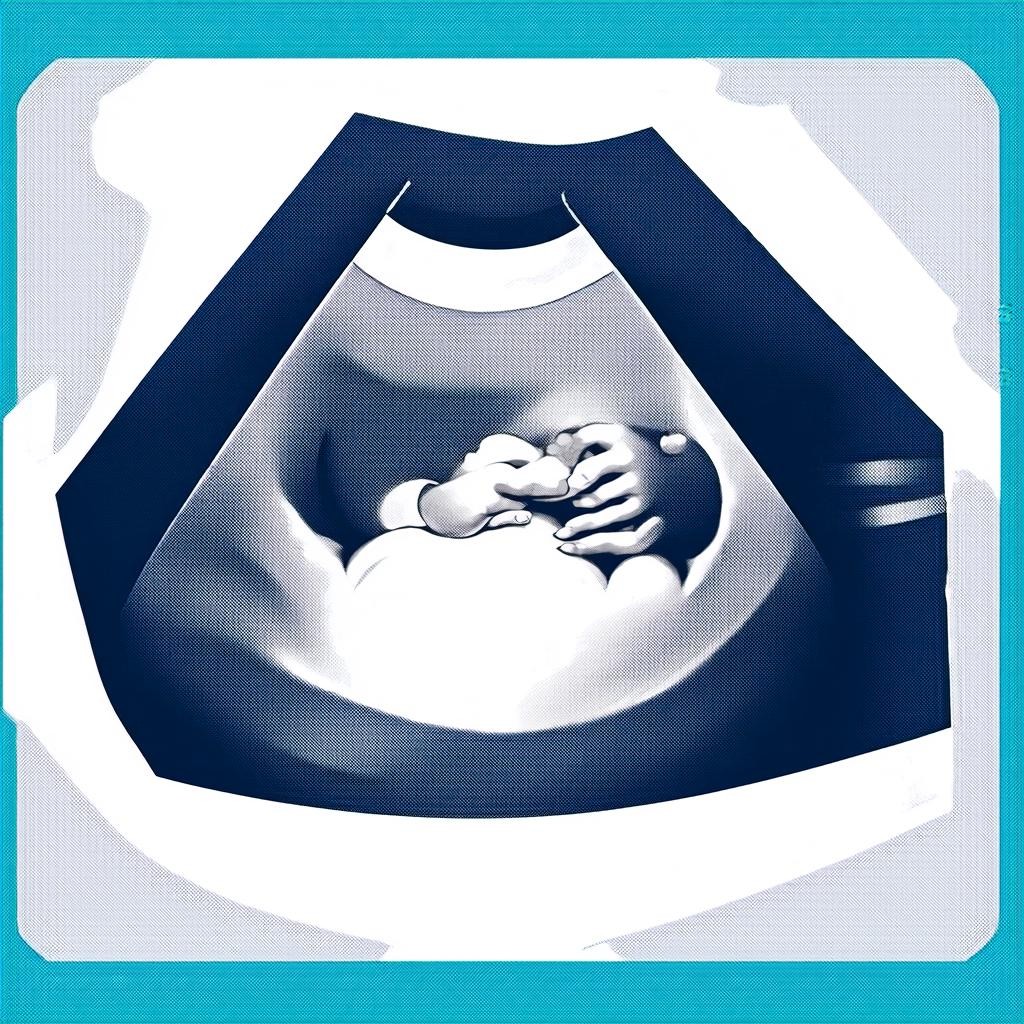

Первое УЗИ при беременности: сроки и важность

Первое УЗИ при беременности — это важный этап, который позволяет убедиться в правильном развитии плода и исключить возможные патологии. Многие будущие мамы задаются вопросом: когда же нужно проходить это исследование? Обычно первое УЗИ назначают на сроке 10-14 недель. Это оптимальный период для оценки состояния эмбриона и определения точного срока беременности.

Помните, что первое УЗИ — это не только медицинская процедура, но и возможность впервые «увидеть» своего малыша. Многие родители сохраняют первые снимки как памятный момент.